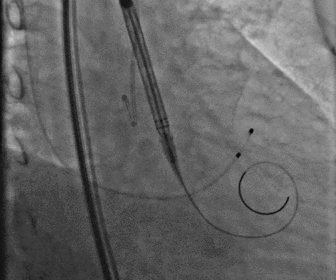

无鞘法上输送器

图片

定位胶囊腔